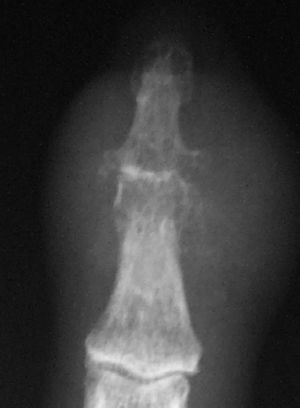

On hand x ray there was evidence of degenerative changes on metacarpophalangeal, interphalangeal, and carpometacarpal joints. The distal interpalangeal joint of the second finger presented soft tissue swelling, with a reduction in joint space and large erosions (Fig. 1). Ecocardiography and serial blood cultures were negative.